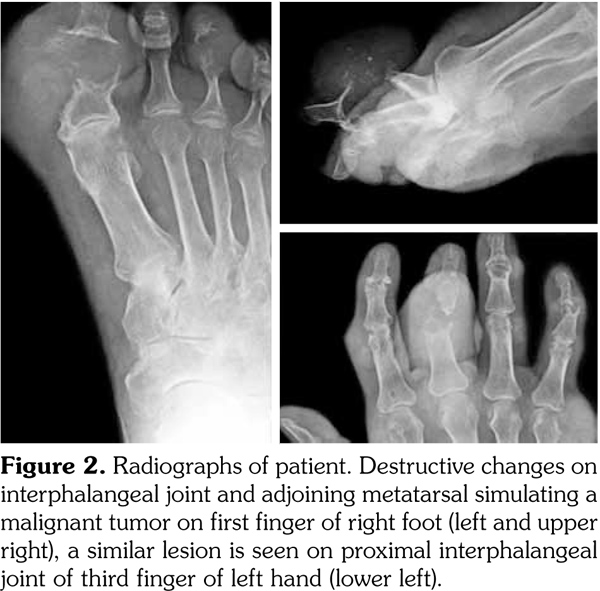

Radiography showed destruction on the IPJ and adjoining metatarsal simulating a malignancy on the first finger of right foot. A similar lesion was noticed on the proximal IPJ of the third finger of the left hand (Figure 2). Besides, soft tissue swellings, periarticular erosions, and osteophytes were seen. On sonography, a few echogenic foci compatible with nephrolithiasis were detected in the right kidney.

There is limited number of papers reporting gouty tophi that mimics malignancy radiologically.(9-13) The hand and foot lesions in our case had atypical radiographic findings with destructive bone and joint changes simulating a malignancy. Roentgenographic changes in gouty arthropathy are not sufficiently sensitive and specific for the diagnosis. Usually, acute gout does not show any abnormality in plain radiographs. Soft tissue prominence and discrete osteoporosis may rarely be present, particularly in the subchondral region.(14) Typical well-defined, “punched out,” periarticular erosions with overhanging edges are not seen until six to 12 years after the initial acute attack. Other radiographic characteristics are normal mineralization, joint space preservation, and asymmetric polyarticular distribution.(15) To the best of our knowledge, extensive bone destruction mimicking lytic bone metastasis and pathologic fracture has not been reported previously in the literature. There is only one paper reporting a single intraosseous gouty tophus in the second metacarpal causing a pathologic fracture and simulating a malignancy.(9) That case had an ill-marginated lytic and sclerotic legion with a pathologic fracture and periosteal reaction. However, in our patient, there were destructive changes similar to a primary or metastatic malignant tumor both in right foot and left hand. Pathologic examination of the operated lesion showed a gouty tophus and did not reveal a malignancy.